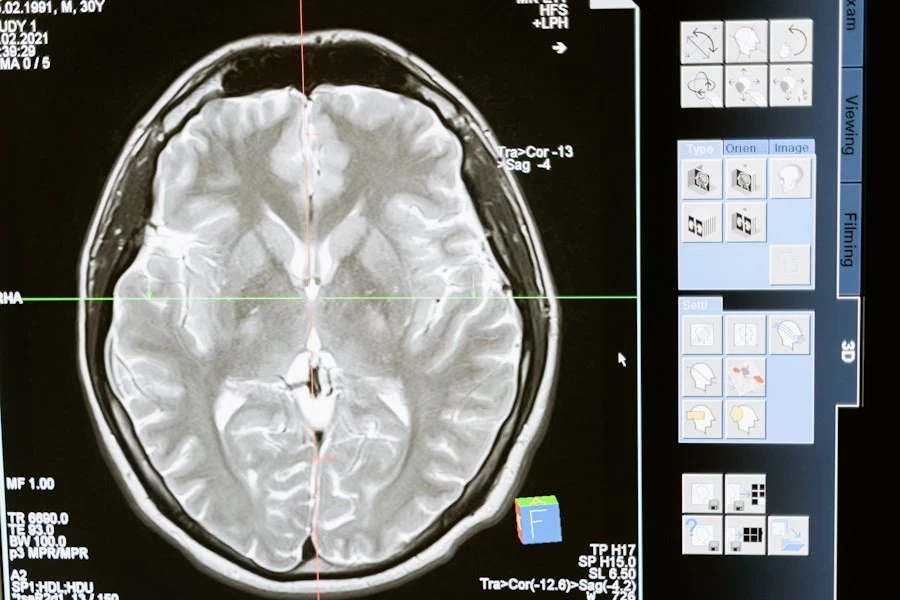

Группа ученых в ходе исследования выявила важную причинно-следственную связь между полимеризацией актина, структурными изменениями в дендритных шипиках и процессами памяти у мышей. Это открытие предлагает новый взгляд на механизмы, лежащие в основе формирования и сохранения памяти в мозге.

Согласно публикации на Science Advances, синаптическая пластичность, способность мозга изменять свою структуру в ответ на опыт и обучение, считается ключевым фактором формирования памяти. Однако, до недавнего времени не было четкого понимания о том, каким образом полимеризация актина, ответственная за стабильность дендритных шипиков — важных структурных элементов нейронов, связанных с образованием синапсов, влияет на кодирование памяти.

Исследователи использовали специально созданную форму протеинкиназы LIMK1, которая направленно воздействует на ADF/кофилин, ключевой модификатор актина. После активации этой формы LIMK1 в организме мышей, было отмечено долговременное увеличение дендритных шипиков и усиление синаптической передачи в гиппокампе, области мозга, играющей важную роль в формировании памяти.